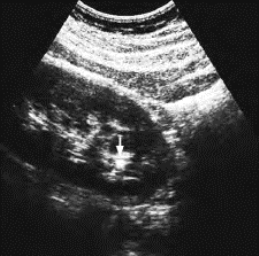

图29-12 肾结石声像图

左肾下极集合系统内点状强回声(箭头所示)

(1)肾集合系统回声区内见到强回声,可呈团状、弧形带状或点状,其后方有声影。

(2)可伴肾积水图像,肾盂扩大呈无回声区,内有强回声,后方有声影。